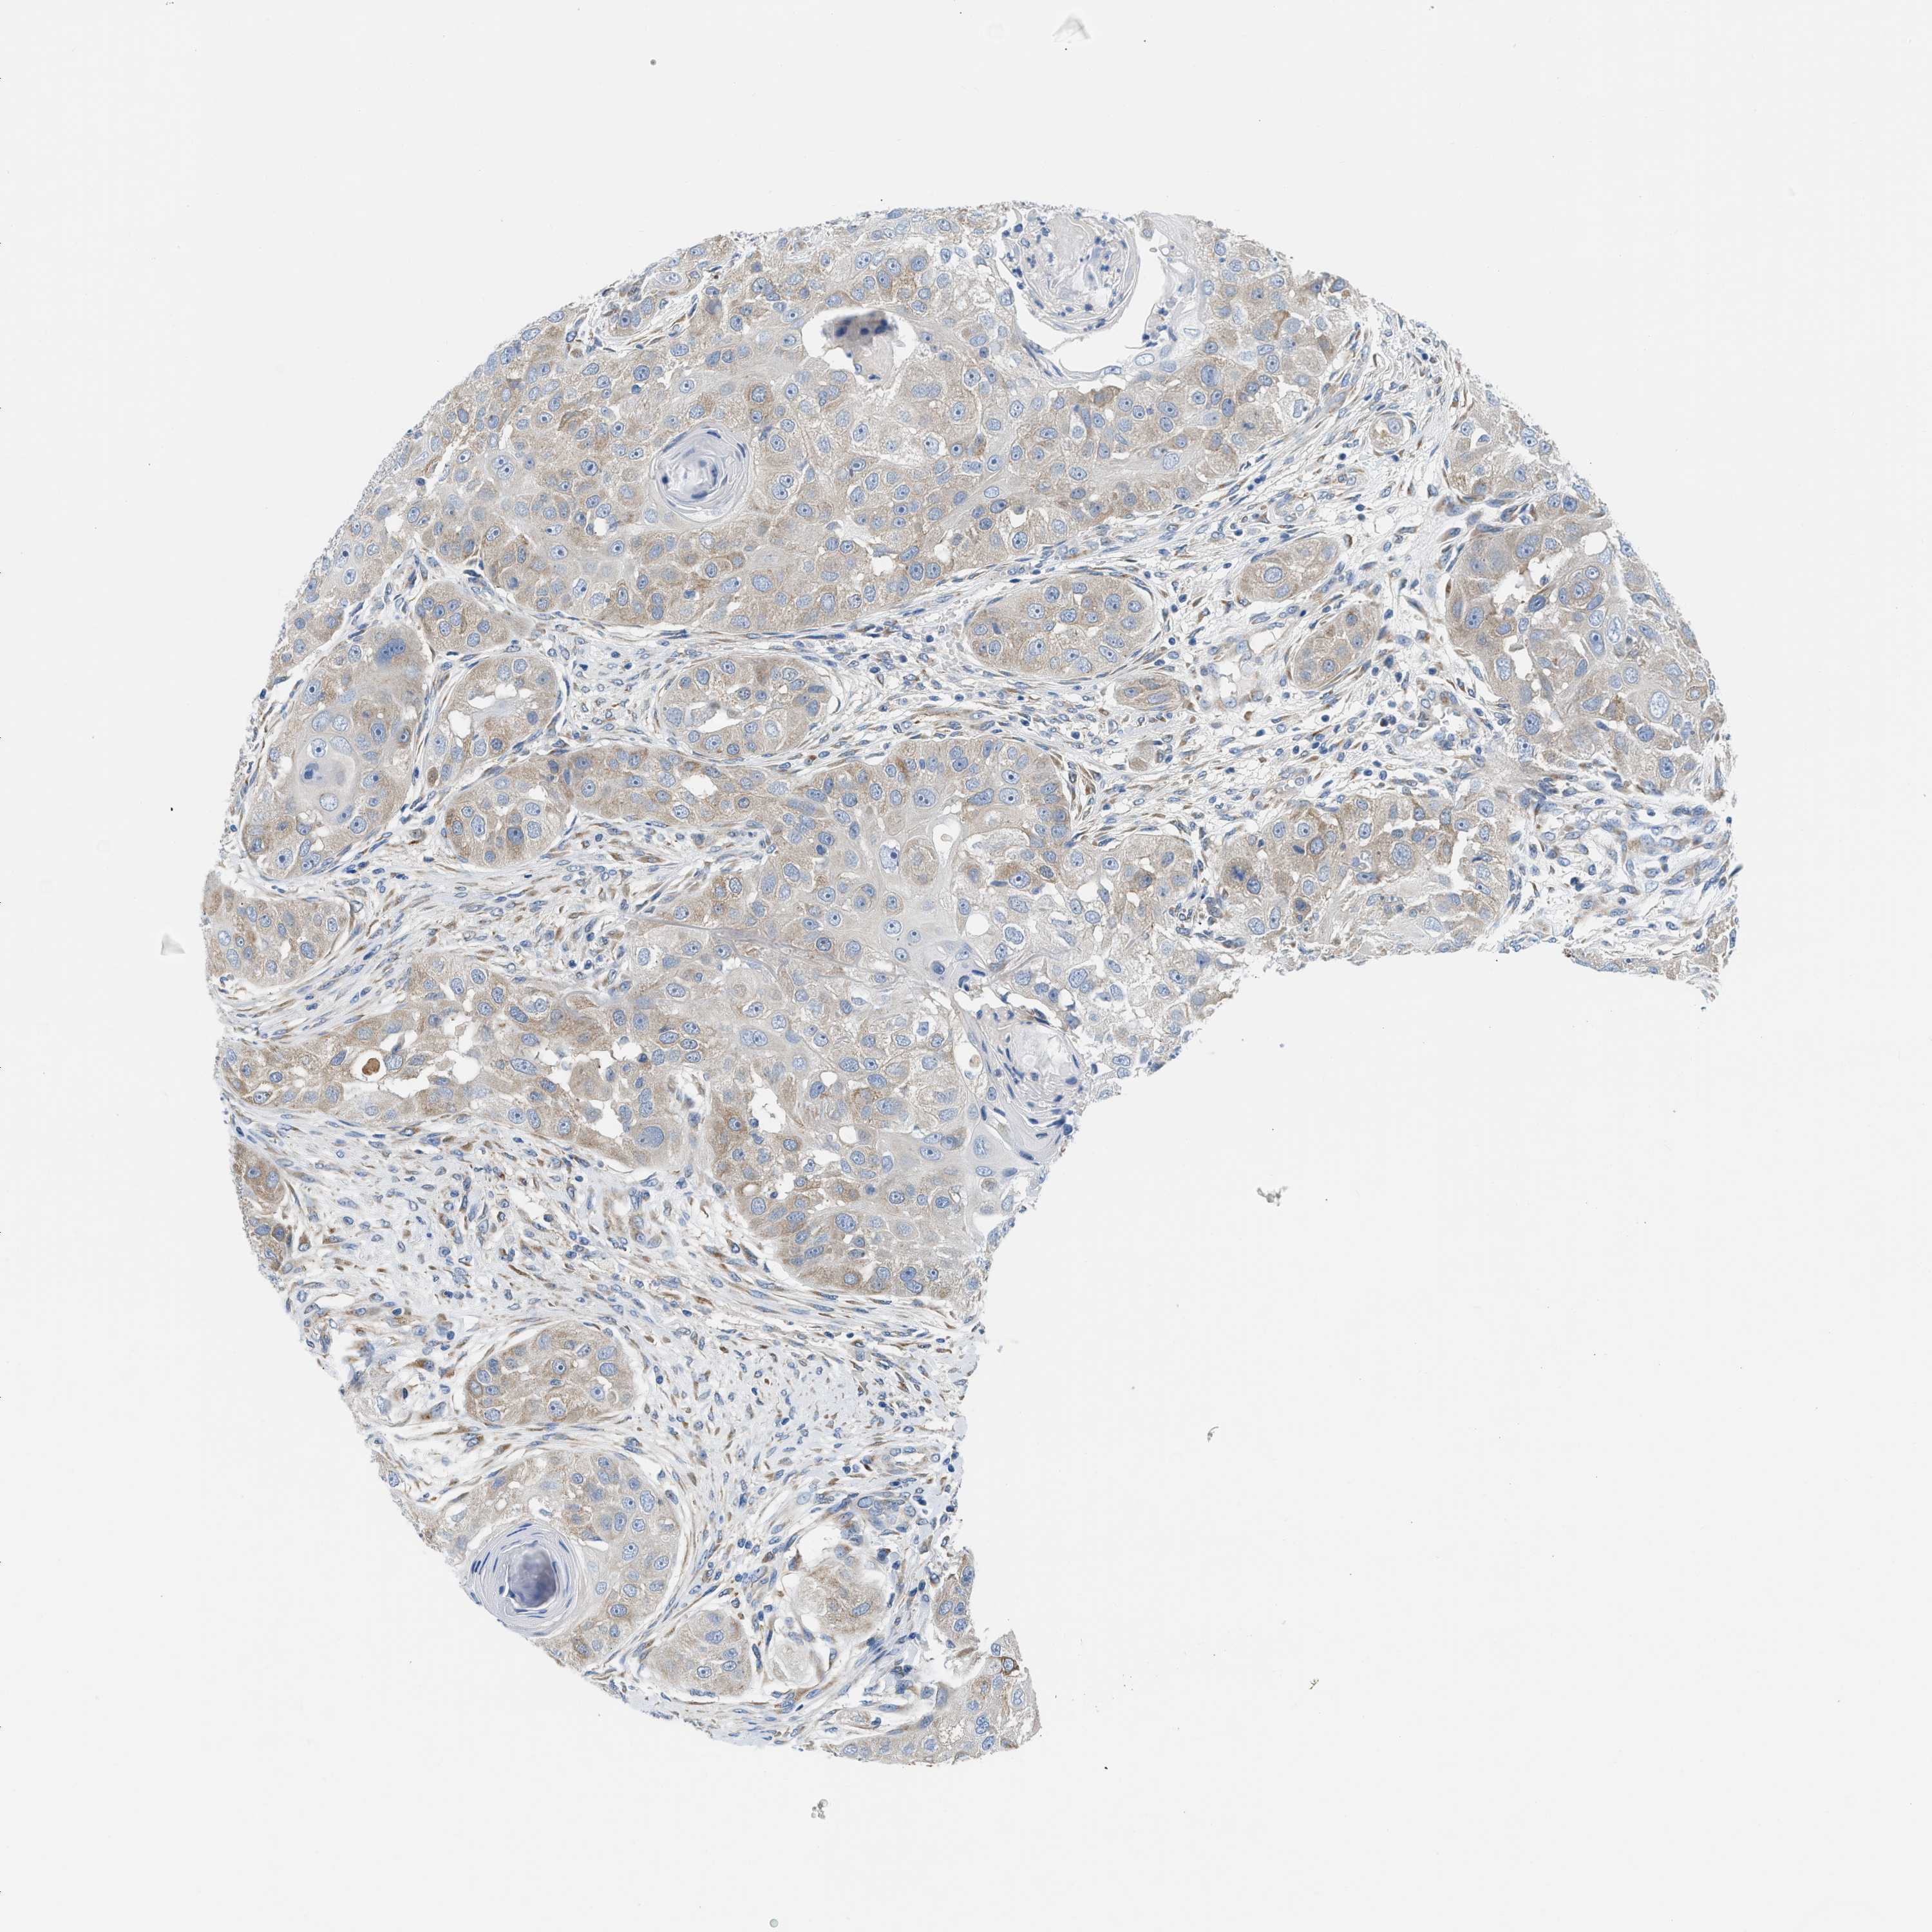

HEAD AND NECK CANCER - Protein expressioni

A mouse-over function shows sample information and annotation data. Click on an image to view it in a full screen mode. Samples can be filtered based on level of antibody staining by selecting one or several of the following categories: high, medium, low and not detected. The assay and annotation is described here.

Antibody stainingi

Antibody staining in the annotated cell types in the current human tissue is reported as not detected, low, medium, or high, based on conventional immunohistochemistry profiling in selected tissues. This score is based on the combination of the staining intensity and fraction of stained cells.

Each image is clickable and will lead to virtual microscopy that enables deeper exploration of all samples and also displays staining intensity scores, fraction scores and subcellular localization as well as patient and tissue information for each sample.

Antibody HPA018525

Squamous cell carcinoma, NOS

Squamous cell carcinoma, metastatic, NOS

Adenocarcinoma, NOS